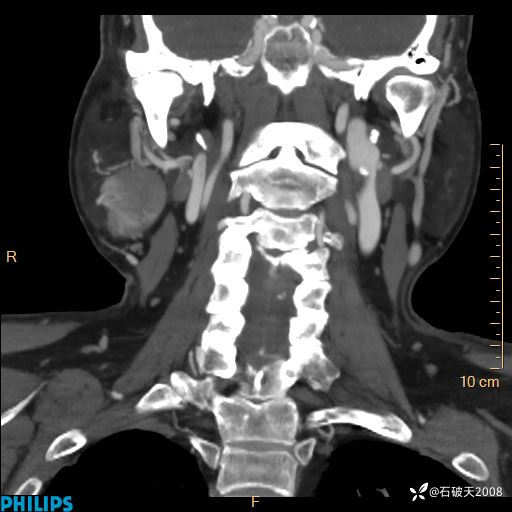

平扫